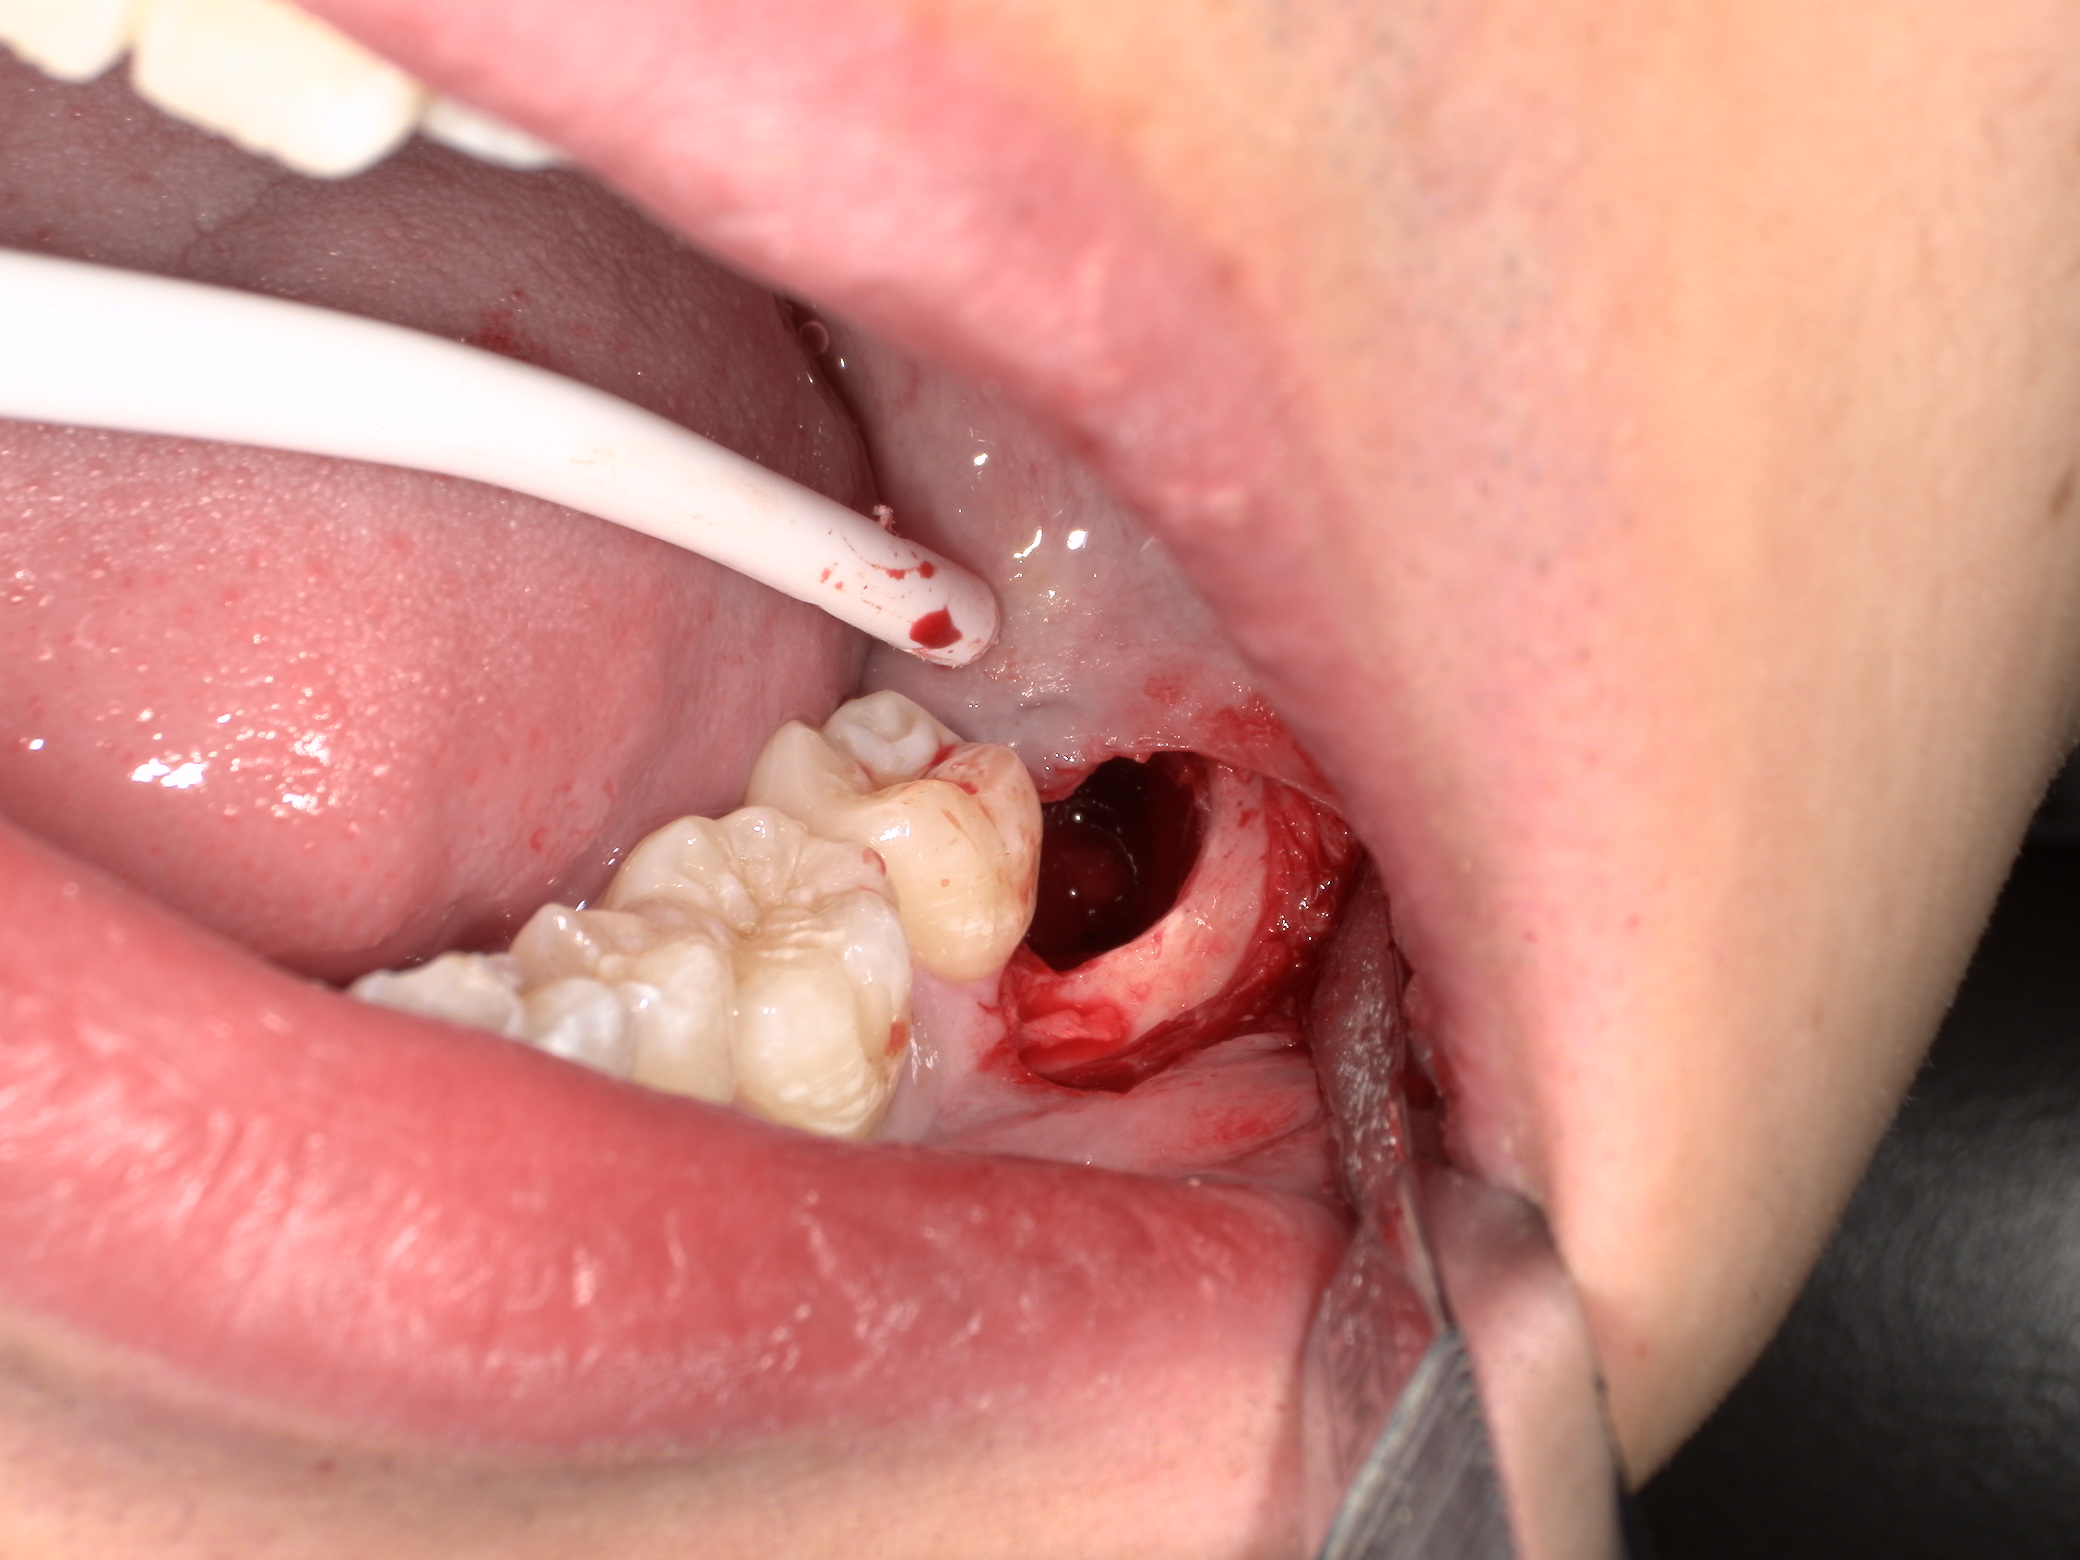

頭を囲む骨はなくなり、親知らずの歯冠部が見えてきましたがまだ抜けません。歯は基本的に頭側の方向にしか抜けません。

斜めに向いているのでこのままでは手前の歯にぶつかってしまいます。